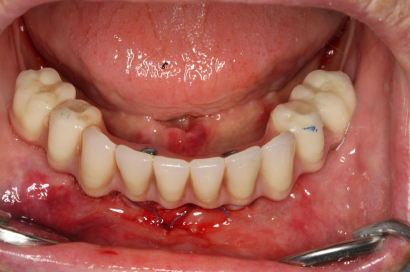

V případě chybění většího počtu zubů v postranních úsecích čelistí je možné ošetření pomocí implantátů, které nahradí ošetření pomocí snímacích náhrad kotvených na zbývajících zubech nebo patře.

Podmínkou je opět dostatečné množství kosti.

Protetické řešení může být pomocí můstku, který je kotvený na implantátech nebo pomocí jednotlivých korunek na implantátech.

V zásadě je možné do těchto můstků zařadit i přirozené zuby, zejména pokud je potřeba tyto zuby ošetřit proteticky

- korunkami. Korunky nebo můstky mohou být na implantáty nacementovány nebo přišroubovány.

Zdravé zuby zůstanou zachovány a přitom náhrady jsou pevné, jako na vlastních zubech